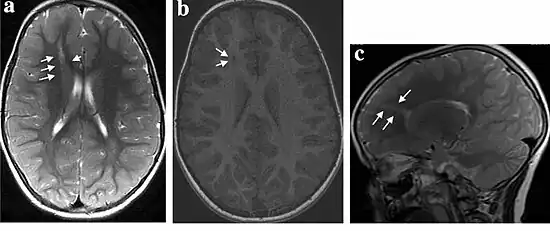

| MRI of a child experiencing seizures. There are small foci of grey matter heterotopia in the corpus callosum, deep to the dysplastic cortex. (double arrows) | |